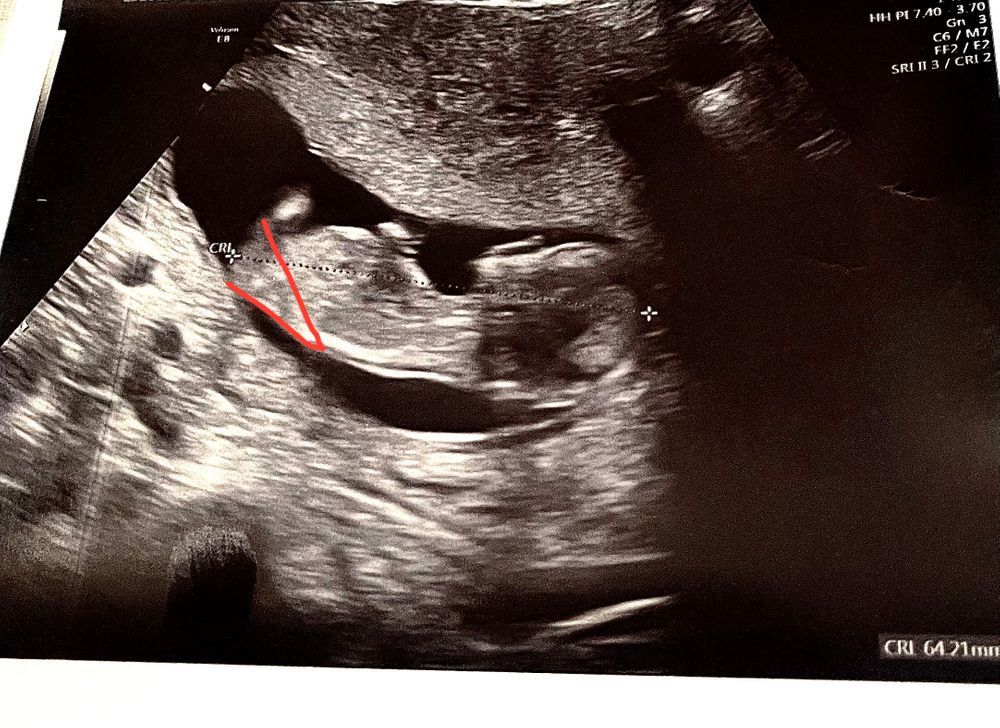

Первый скрининг 🍼❤️

Вроде на мальчика похож)))

Юлия , бугорок, перпендикулярен позвоночнику) у девочек он параллельно находится) Изображение

Бугорка не видно, но похожа на девочку ☺️

Определение Пола Челябинск Девочки, как думаете, кто?